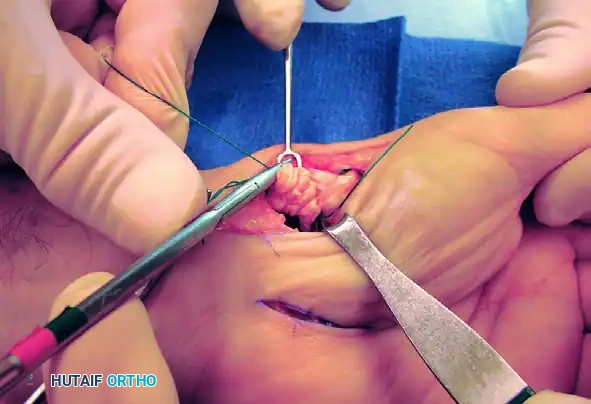

Tendon Routing and Suspensoplasty

- Tendon Passage: Pass the harvested FCR tendon strip through the newly created bone tunnel. Hold the tendon perpendicular to the index metacarpal shaft.

- Suspension: Approximate the index and thumb metacarpal bases by applying slight ulnarly directed pressure on the thumb metacarpal. Firmly secure the FCR tendon to the APL bony insertion using 2-0 braided nonabsorbable sutures. This step acts as a "suspensoplasty," preventing proximal migration of the thumb metacarpal.

Figure B: FCR tendon passed through the bone tunnel while the index and thumb metacarpal bases are approximated.

Intraoperative view demonstrating the suspension of the first metacarpal.

- Intermetacarpal Securing: Pass the FCR tendon between the thumb and index metacarpal bases and secure it to itself with the same nonabsorbable suture.

*Figure C: FCR tendon passed between